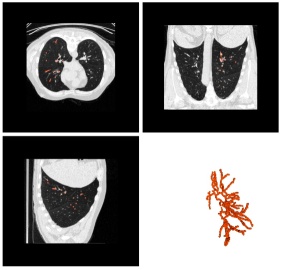

3.1.3 Pulmonary Data

This dataset was provided by the Extraction of Airways from CT 2009 (EXACT09) challenge pulmonary and contains pulmonary vessels inside the lungs.

The goal of this challenge was to compare the results of various algorithms to extract the airway tree from CT scans using a common dataset and performance evaluation procedure. The challenge provides training and testing datasets, and there is also a reference data available for the pulmonary airways but not for the pulmonary vascular network, so, our evaluation in this case was qualitative.

Figure 16 shows the results produced by our method on this data set. It can be seen that most of the vascular network, including bifurcations, were found. Even though this kind of evaluation is not numerical, the results show the potential of the method, specially if one takes into consideration that a single seed point was used.